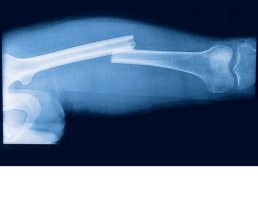

Пациента доставили на скорой с адской болью, отёком и здоровенной гематомой в самом деликатном месте. Врачи диагностировали «перелом» пениса — травму настолько редкую, что хирурги больницы даже не вспомнили, когда в последний раз с таким сталкивались.

Как мужчина умудрился так «отличиться» — тайна, покрытая мраком. Но эксперты говорят, что такие травмы обычно случаются либо в порыве страсти, либо в быту. Как объяснил уролог Дмитрий Салихов, это не настоящий перелом (кости-то там нет), а разрыв белочной оболочки кавернозных тел от резкого удара или давления.